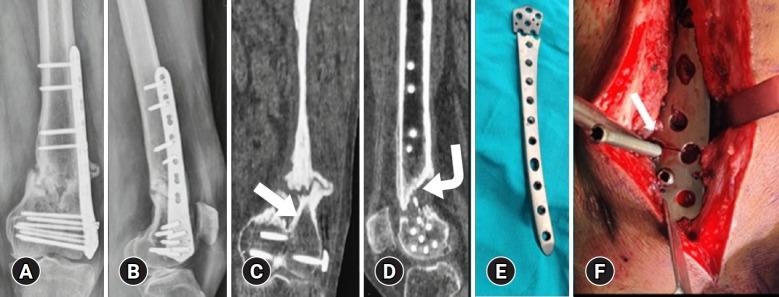

This study investigated 24 aseptic and 3 septic nonunions of distal femur fractures, classified as AO/OTA type C, that were previously managed with open reduction and internal fixation using only a lateral locked plate. Revision surgery involved replacing the broken 5.0-mm lateral locked plate, supplementing the medial side with a 4.5-mm T-plate, and applying bone grafting at the fracture site. Septic cases were managed using a staged approach with dual implant application.

方法

本研究调查了24例无菌性和3例感染性股骨远端骨折不愈合病例,均为AO/OTA C型,此前仅使用外侧锁定钢板进行切开复位内固定治疗。翻修手术包括更换断裂的5.0毫米外侧锁定钢板,在内侧补充一块4.5毫米的T形钢板,并在骨折部位进行植骨。感染病例采用分期双钢板置入的方法处理。